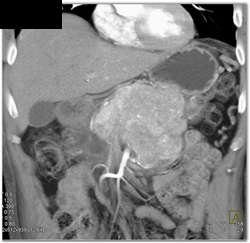

Islet Cell Tumor